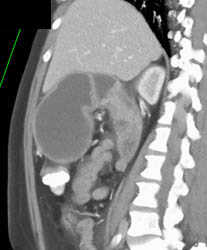

Antral Carcinoma